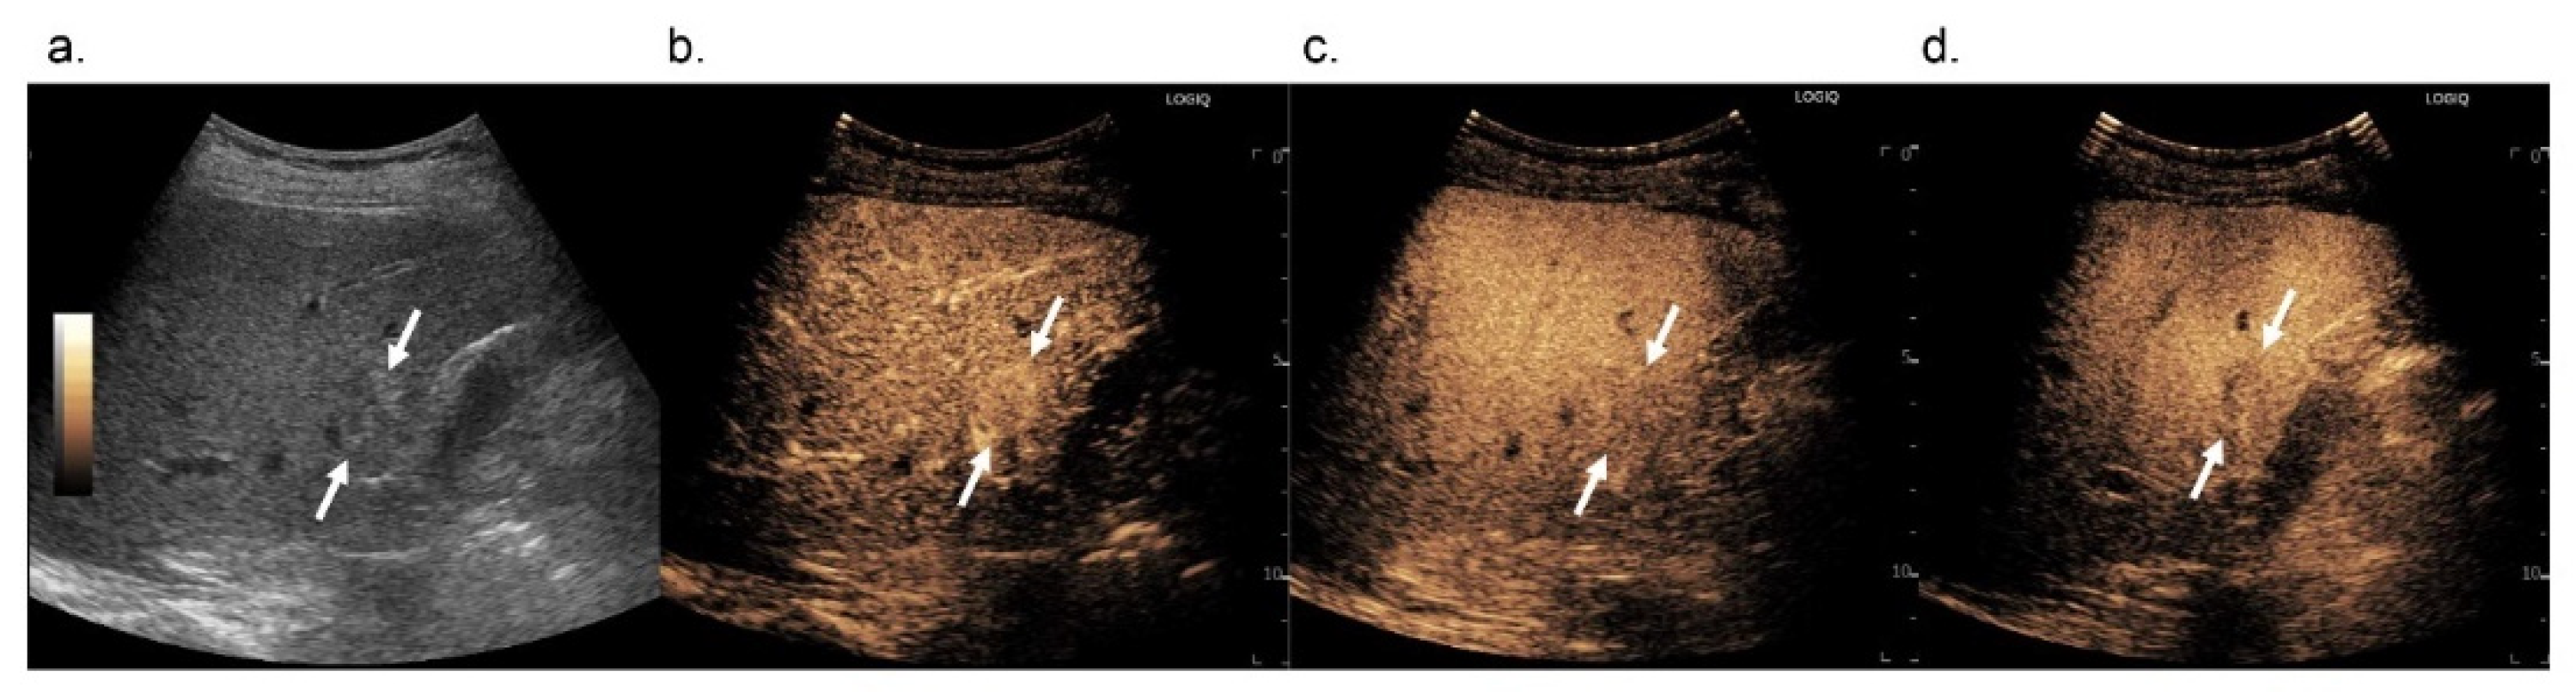

3.2.1. Arterial Phase

3.2.2. Washout